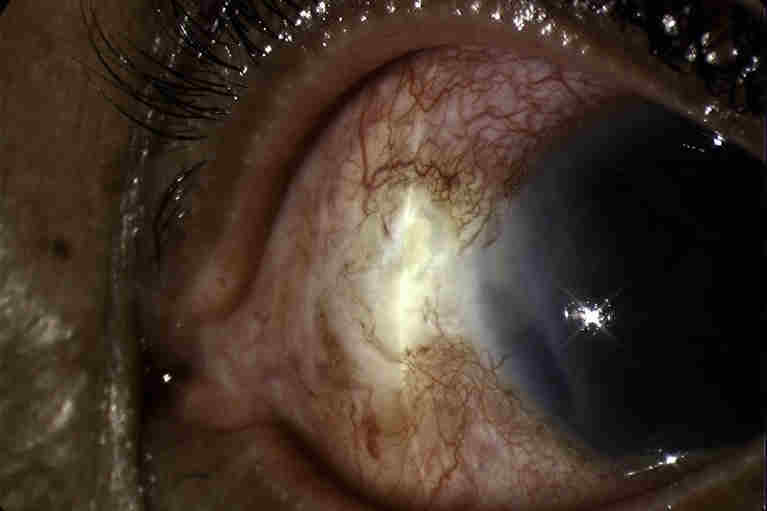

Fig. 4 Fungal scleritis with hypopyon

Whilst most scleritis is immune mediated, around 5-18% of scleritis may be infectious. It is important to identify these cases to allow treatment of the underlying infection and to avoid clinical worsening from inappropriate use of immunosuppression. Pseudomonas aeruginosa is the most common organism, particularly following trauma, however multiple other organisms may be implicated, including fungi, mycobacterium species and also viruses such as herpes zoster and simplex. Red flags that should alert the clinician to the possibility of infection include: history of prior trauma or surgery, although there may be a long delay to presentation; use of topical corticosteroid prior to presentation with scleritis; other immune compromising conditions such as diabetes, necrotising scleritis and scleral abscess formation; and pronounced anterior chamber inflammation and hypopyon4. Diagnosis is often delayed in infectious scleritis and organisms may be difficult to culture, frequently requiring scleral biopsy.